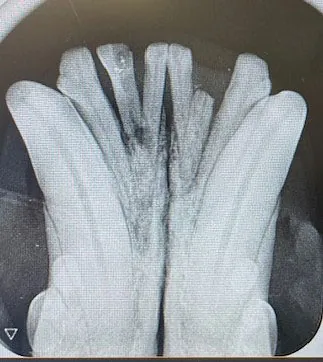

Moderne Diagnostik – direkt vor Ort

• Digitales Röntgen (Ganzkörper & Dental)

• Inhouse-Labor: Blutbild, Organprofile, Schilddrüse, Entzündung, Harnstatus

• Zytologie: Haut, Ohren, Tumore, Abklatsch- & Punktionsdiagnostik

• Tonometrie, Blutdruckmessung, EKG, endokrinologische Tests